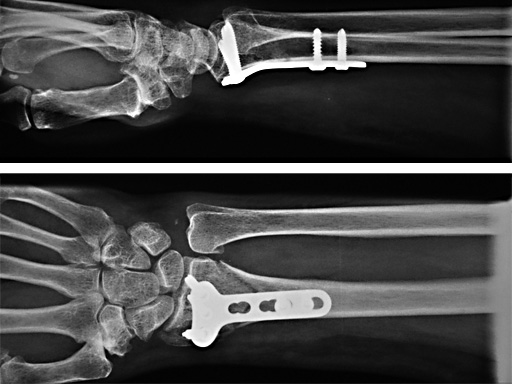

2.4 mm LCP Distal Radius Plate

- LCP 3.5 mm distal radius study, involving centers mainly using the 3.5 mm LCP system (10 centers).

- LCP 2.4 mm distal radius study, focused on the 2.4mm LCP system (6 centers).